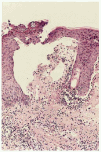

La histología en las lesiones urticarianas consiste en edema dérmico con infiltrado inflamatorio de linfocitos y eosinófilos de localización perivascular con algunos eosinófilos intersticiales. Previamente a la formación de la vesícula se pueden apreciar eosinófilos dispuestos linealmente y agregados a la unión dermo-epidérmica. Posteriormente se forma la ampolla de localización subepidérmica (fig. 3). En ocasiones se puede apreciar espongiosis eosinofílica. Algunos autores han descrito necrosis de queratinocitos en estadios iniciales. Se ha determinado depósito de las proteínas de los gránulos de los eosinófilos a nivel intersticial y adyacente a la membrana basal24. Con el microscopio electrónico aparte de los datos previos se puede apreciar que la ruptura de la membrana basal se localiza a nivel de la lámina lúcida8.

Fig. 3. Herpes gestationis. Histología: ampolla subepidérmica con cúmulo inflamatorio en unión dermoepidérmica (henatoxilina-eosina x20).